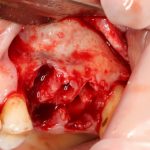

Для получения костного блока, мы открываем донорскую зону, наружную косую линию нижней челюсти.

Получение костного аутотрансплантата.

Здесь потребуется пародонтологический зонд с миллиметровой разметкой или какой-то другой измерительный прибор (операционная линейка). Ранее по КЛКТ я измерил костный дефект, теперь нужно нанести границы будущего костного блока на донорскую зону.

Для получения костного блока мы использовали ультразвуковую пьезохирургическую систему. Это самый удобный и безопасный инструмент для проведения подобных манипуляций. С помощью него мы сформировали и выделили костный блок. Он должен отделяться легким движением остеотома или элеватора. Как это сделать правильно — читай здесь>>